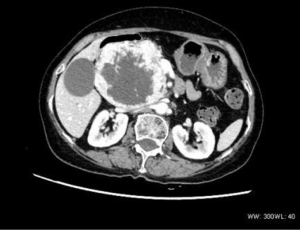

The single pancreatic tumor contained cystic and solid components, with local separation and spotty calcification, together with continuous and obvious uneven enhancement (Figure 5).

The ovarian tumor case presented with “honeycombed” changes (Figure 6), with obvious uneven enhancement and bone metastasis.